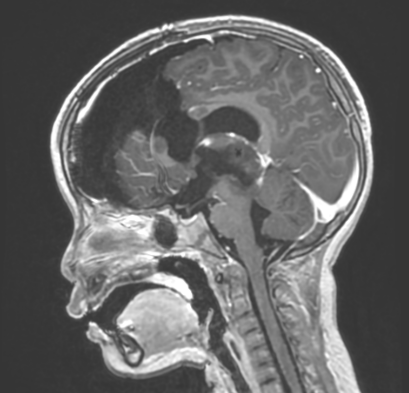

患者女,4岁6月,症状为双上肢震颤、右侧踝阵挛。院外头颅MRI平扫示松果体区占位性病变并梗阻性积水、间质性脑水肿。在上海儿童医学中心张江院区神经外科进一步行头颅MRI平扫+增强检查,于松果体区见团块样占位,大小约29.4*26.7*26.5mm,T1WI低信号,T2WI稍高信号,有明显不均匀强化。影像学诊断为右侧丘脑至松果体区占位,考虑恶性肿瘤。

患儿术前MRI图像